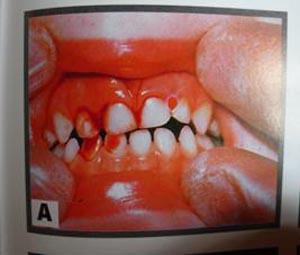

乳牙牙震荡

5、外伤挫入:根据X线片和临床检查结果,确定挫入的方向和程度,判断是否影响恒牙胚,如果没有对恒牙造成影响,可暂时保留乳牙,反之应拔出受伤乳牙。

6、牙脱位:未伤及恒牙胚的乳牙,可暂时观察,或根据家长的要求作松牙固定和调和处理,但要告知家长一旦出现不适必须拔出。